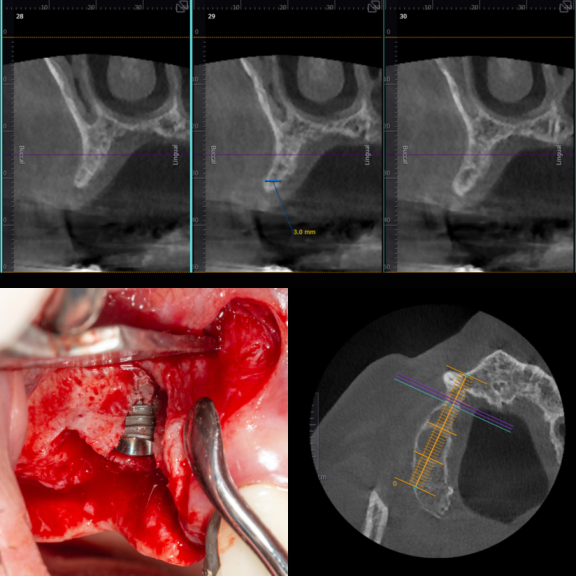

İmplant etrafındaki kemik açıklığını kemik grefti ile tedavi ettiğimiz vakamız